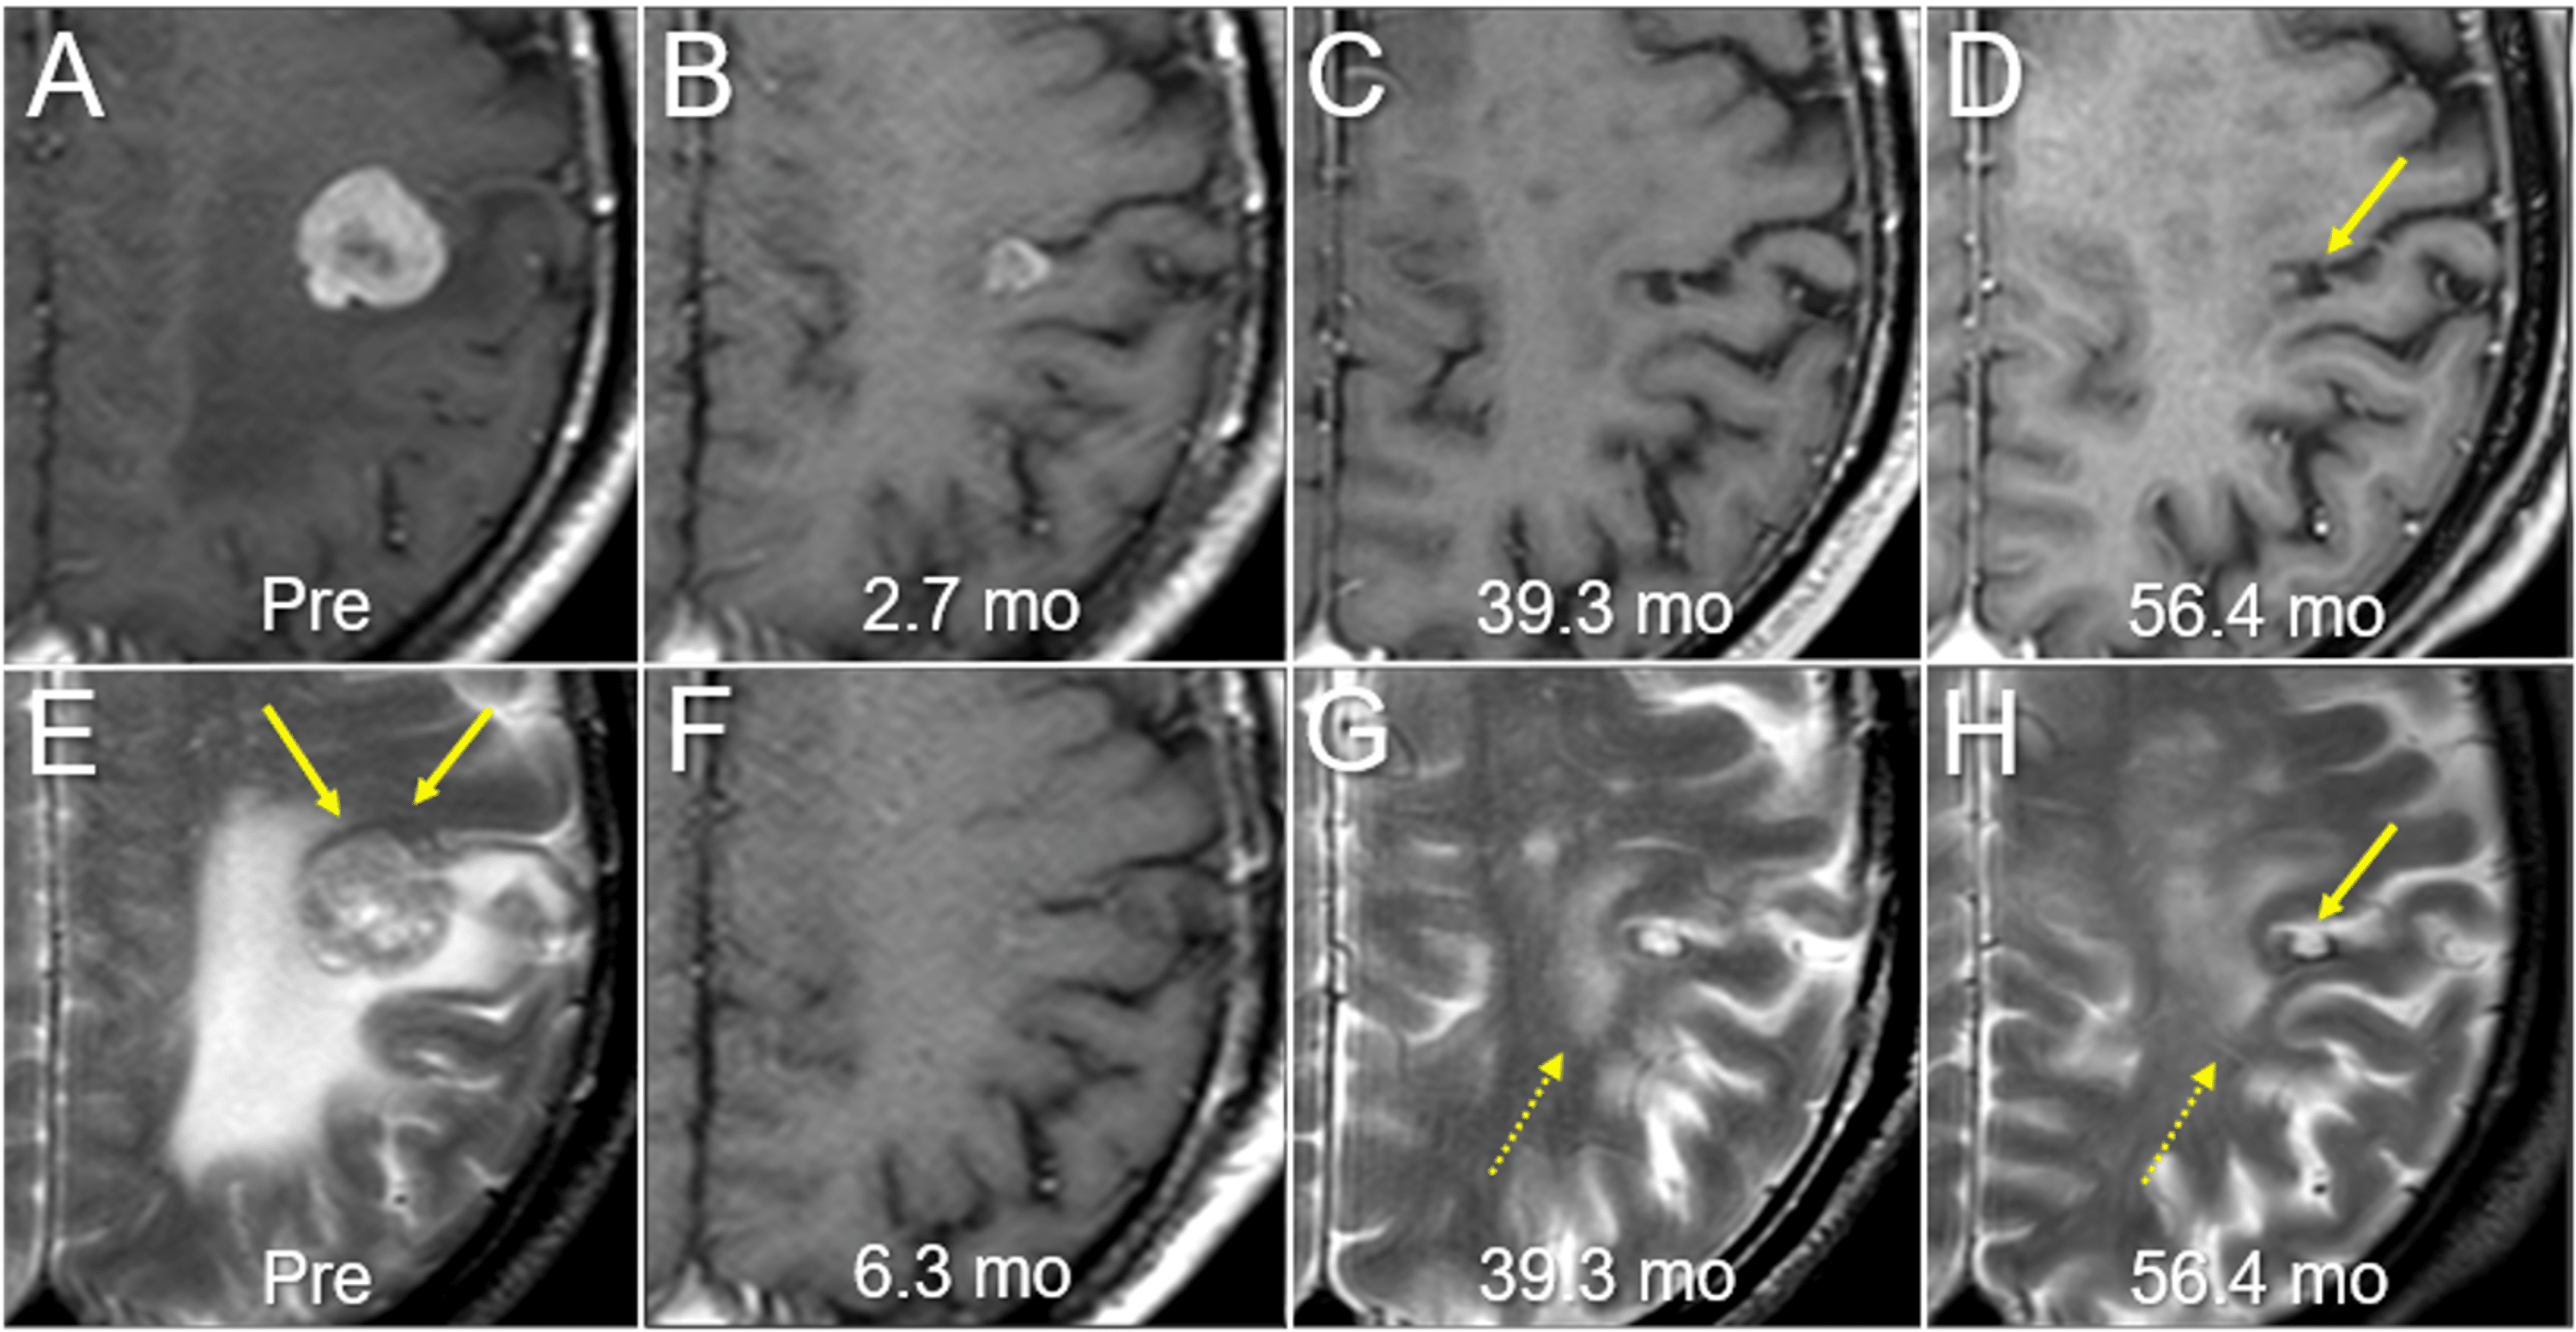

Cureus FiveYear Sustained Complete Remission With Minimal Adverse

Cureus FiveYear Sustained Complete Remission With Minimal Adverse Radiosurgery Painful Gamma knife radiosurgery is a type of radiation therapy. — radiation oncologists and neurosurgeons use stereotactic radiosurgery to treat certain brain conditions —. Importanceconventional external beam radiotherapy (cebrt) and stereotactic body radiotherapy (sbrt) are commonly used. It can be used to treat tumors, veins that have developed differently than. the most common acute complication of brain rt is. Radiosurgery Painful.